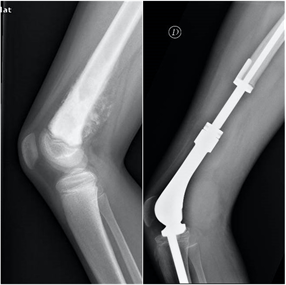

Los sarcomas óseos son tumores óseos muy infrecuentes, con una incidencia aproximada de 1 caso por cada 100.0000 habitantes.  El Osteosarcoma es el tumor óseo primario maligno más frecuente en la infancia, seguido por el el Sarcoma de Ewing. En las radiografías se suelen evidenciar lesiones líticas, permeativas, con destrucción ósea, reacción perióstica y afectación del los tejidos blandos cercanos. Estos pacientes ,además de dos proyecciones radiográficas, precisarán estudios complementarios de imagen, biopsia, estudio de extensión para descartar diseminación pulmonar, y valoración multidisciplinar. La cirugía oncológica de salvamento de extremidad y reconstrucción es la técnica de elección.

En el cáncer diseminado el tratamiento de las metástasis suele ser paliativo, mediante estabilización de la fractura con osteosíntesis o implante de prótesis. En ocasiones la osteosíntesis se suplementa con aporte de cementos biológicos para aumentar la estabilidad o se realiza radioterapia complementaria. En casos de metástasis únicas, el tratamiento quirúrgico radical de la metástasis puede estar indicado, lo que hace necesaria la valoración conjunta de traumatología oncológica y oncología médica ante la detección de una lesión metastásica ósea en nuestra práctica.

El tumor de células gigantes es una lesión tumoral benigna pero localmente agresiva. Provoca lesiones líticas expansivas que se localizan fundamentalmente en las metáfisis y epífisis de huesos largos. La edad de aparición está entre los 20 y 50 años y se suele localizar con mayor frecuencia en la zona cercana a la rodilla, en la epífisis distal del fémur, en la tibia proximal y en el radio distal. Se describe la presencia de metástasis pulmonares en casi el 5% de los pacientes. Habitualmente el paciente refiere una historia de dolor persistente en torno a la rodilla, con afectación progresiva de la funcionalidad. Las fracturas patológicas suelen aparecer fundamentalmente en casos avanzados, con gran debilidad cortical. En la rodilla puede asociar derrame articular y fracturas osteocondrales por debilidad del hueso subcondral.

Los sarcomas óseos son tumores primarios malignos muy raros que afectan fundamentalmente a niños y adolescentes, aunque también puede aparecer en pacientes mayores de 65 años, en relación con otras enfermedades o radioterapia.  Debemos sospechar la presencia de un tumor maligno primario de hueso en pacientes con imágenes radiológicas de apariencia agresiva, como márgenes mal definidos, lesiones líticas con patrón permeativo, destrucción de las corticales, reacción perióstica e invasión de los tejidos blandos. Si detectamos una lesión de este tipo debemos siempre realizar una valoración multidisciplinar por equipos especializados en Traumatología oncológica y Oncología.